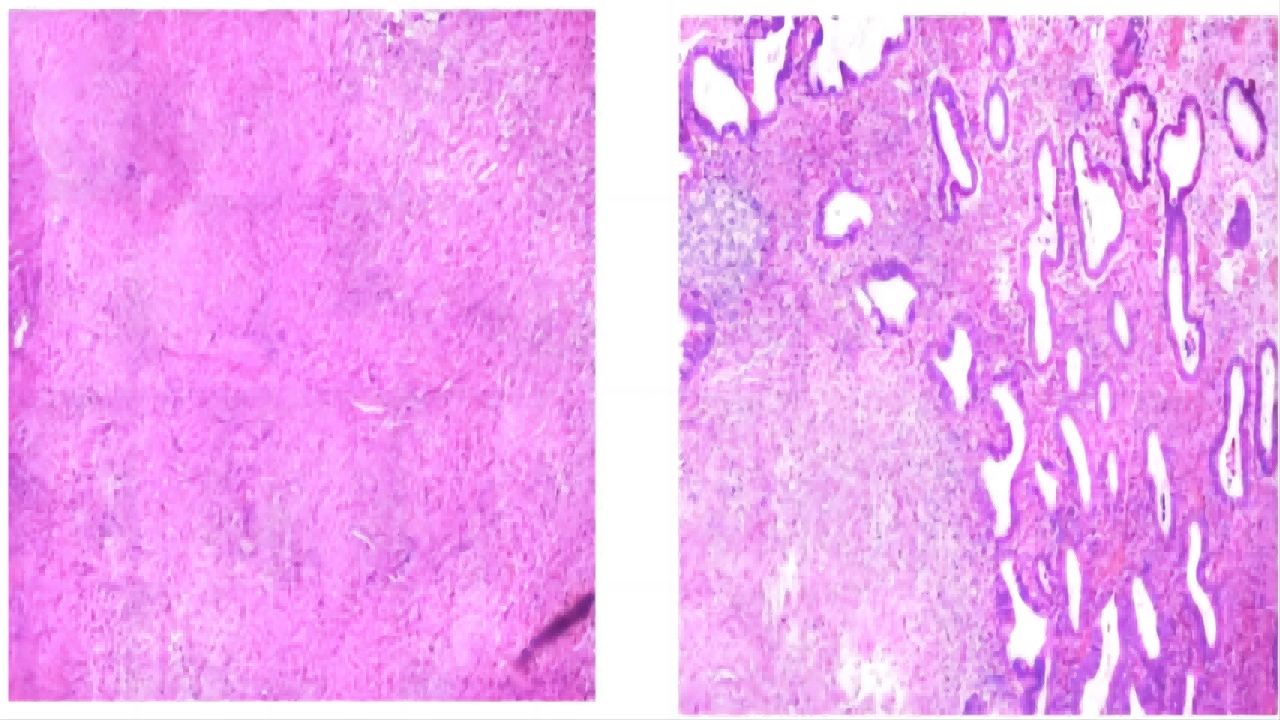

术后病理:(子宫内膜)送检少量子宫内膜呈增殖期样改变,另见小片增生的宫颈管组织。(子宫肌瘤及息肉)平滑肌瘤;子宫内膜息肉。